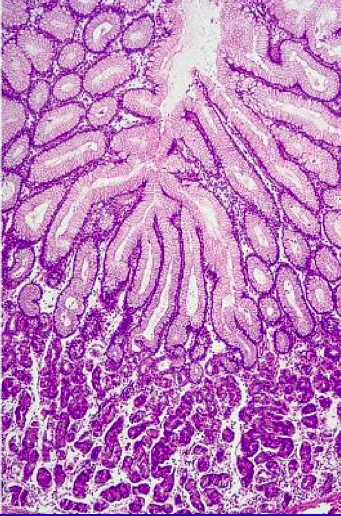

<p>What type of glands are shown here? Describe them</p>

<p>oxyntic; combination of both basophilic and eosinophilic cells</p>

<p>What type of glands are shown here? Describe</p>

<p>mucin glands, pale and eosinophilic</p>